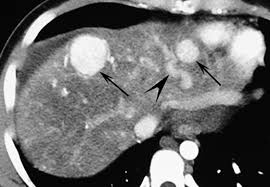

Chiasmata -mə-tə or chiasmas also chiasms 1. Esophageal varices are extremely dilated sub-mucosal veins in the lower third of the esophagus. Located in metro Denver northern Colorado and western Nebraska serving all of the Front Range our team consists of board-certified and fellowship-trained interventional radiologists. This results in hepatic congestion similar to Budd-Chiari syndrome and post-sinusoidal portal hypertension. The patients condition should be monitored throughout the procedure. They are most often a consequence of portal hypertension commonly due to cirrhosis. Toxic injury to liver sinusoids causes sloughing of endothelial cells that embolize to hepatic venules and cause eventual fibrosis of the venules. Coin in the Esophagus. There is no clear consensus regarding the number of occluded veins some authors claim that there should be at least one occluded hepatic vein 7 others state that there are no significant.

Carcinoma of the Colon. Budd-Chiari syndrome a blockage in one or more veins that carry blood from the liver back to the heart. And coumarin skin necrosis adrenal gland hemorrhage and infarction. Toxic injury to liver sinusoids causes sloughing of endothelial cells that embolize to hepatic venules and cause eventual fibrosis of the venules. Chiari malformation CM is a structural defect in the cerebellum characterized by a downward displacement of one or both cerebellar tonsils through the foramen magnum the opening at the base of the skull. Embolism and thrombosis of. La présence dune ou plusieurs affections prothrombotiques est fréquente La prise en charge repose sur un traitement anticoagulant précoce le traitement de l.